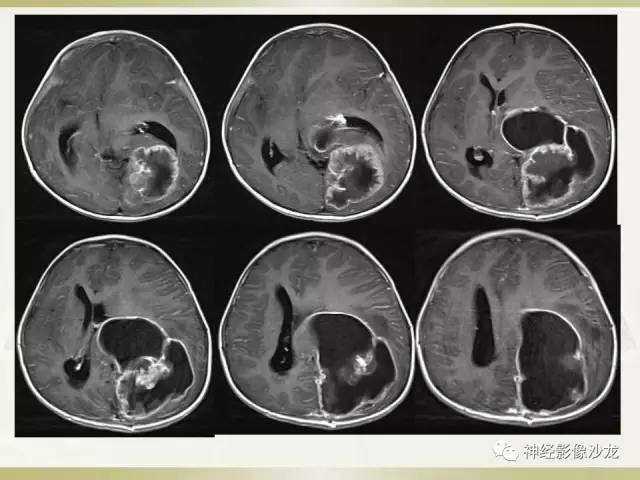

【病例】幕上脑实质内室管膜瘤1例CT及MR影像讨论

囊实性占位,有钙化,实性成分明显强化

周老师说过两大特点,钙化,囊变,白老师说DWI高

其内有钙化,DWI高信号

侧脑室三角区受压

儿童,侧脑室三角区旁、囊变、钙化、出血,下次见到首先考虑啊